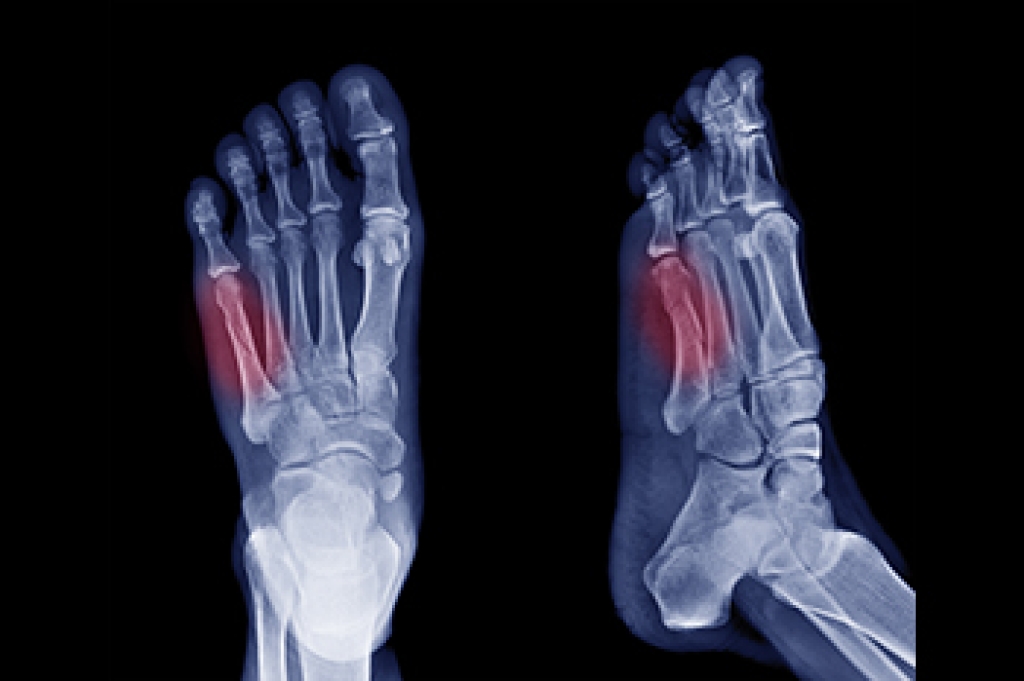

Heel pain is often associated with plantar fasciitis. The plantar fascia is a band of tissues that extends along the bottom of the foot. A rip or tear in this ligament can cause inflammation of the tissue.

Heel spurs are another cause of pain. When the tissues of the plantar fascia undergo a great deal of stress, it can lead to ligament separation from the heel bone, causing heel spurs.